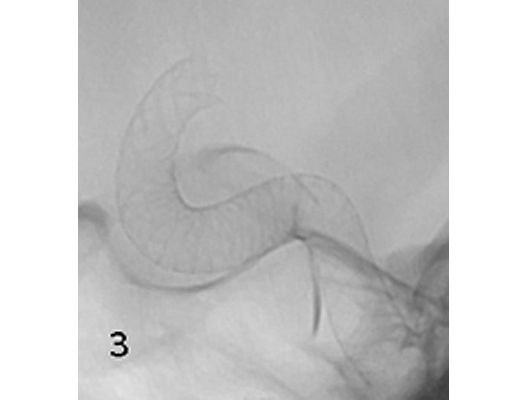

Mit den modernen Verfahren zur Wiedereröffnung von verschlossenen Blutgefäßen können wir Patienten mit Schlaganfall in vielen Fällen helfen. Das folgende Beispiel zeigt die angiographischen Bilder eines Patienten, der mit vollständiger Lähmung der rechten Körperhälfte und einer schweren Sprachstörung eingeliefert wurde. Ursächlich zeigte sich ein Verschluss der linken Halsschlagader, vermutlich auf dem Boden einer arteriosklerotischen Einengung (Bild 1). Das Gefäß wurde daraufhin mit einem Stent wiedereröffnet (Bild 2). Zusätzlich zeigte sich ein Verschluss der Endstrecke des Gefäßes durch Blutgerinnsel (Bild 3). Diese konnten vollständig entfernt werden (Bild 4). Der Patient erholte sich nach der Behandlung innerhalb weniger Tage vollständig.